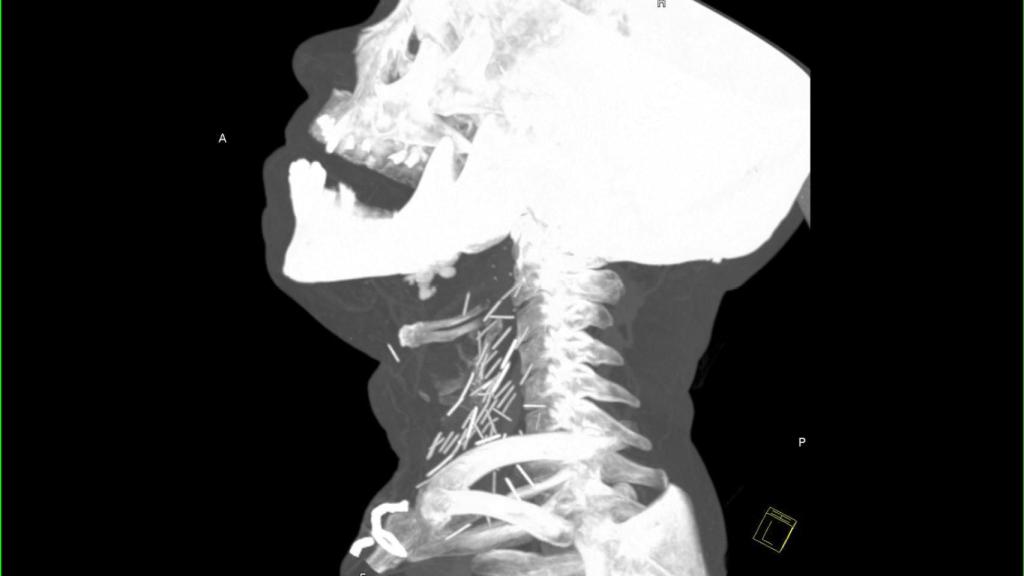

Radiografía de un hombre con agujas rotas incrustadas en el cuello.

Aunque el caso data de hace 4 años, no fue hasta diciembre de 2015 cuando aparecieron las llamativas imágenes que anteceden a estas líneas en un subforo de Reddit -una de las comunidades de usuarios más grandes de internet-. En ellas se puede ver una radiografía del cuello de un adicto a la heroína repleta de agujas rotas.

Según la historia original de Reddit, la radiografía de este paciente apareció a raíz de su visita al servicio de urgencias de un hospital a causa de una neumonía. Tras examinar a este paciente con años de consumo de heroína a sus espaldas, se le hicieron una serie de pruebas y se comprobó que tenía el cuello lleno de agujas.

Las complicaciones asociadas a estas agujas en el interior del organismo tienen que ver con la formación de abscesos -acumulaciones de pus-, lesiones en las arterias e incluso hemorragias internas potencialmente letales. De hecho, cuando un médico va a examinar a un drogadicto, debe tener cuidado para no entrar en contacto con las más que probables agujas que podrían tener incrustadas en la piel.